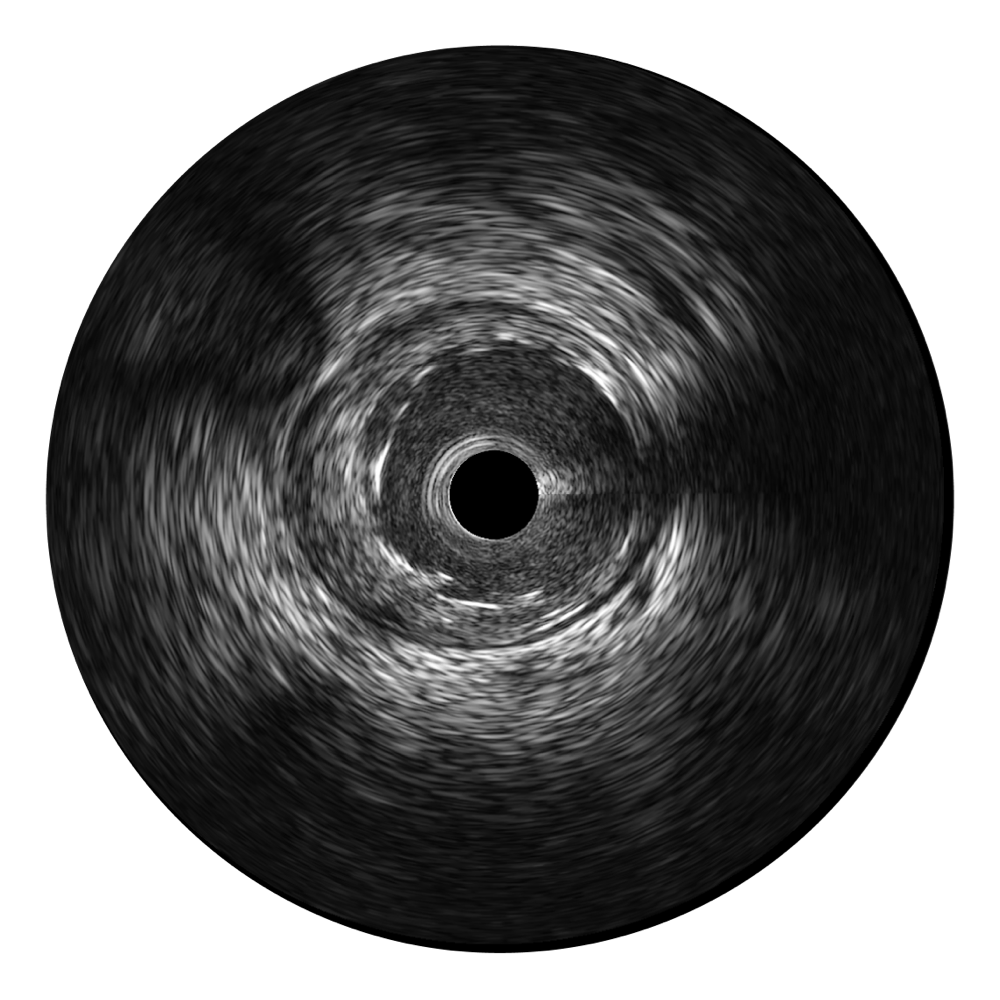

• 云顶集团官网宽频IVUS图像

• 传统IVUS图像

对比传统IVUS导管成像,云顶集团官网宽频IVUS图像的近场支架梁显影更细腻,远场中膜外血管仍清晰可辨,兼顾远中近,兼顾分辨力与穿透深度